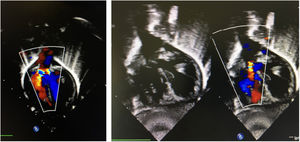

El primer paciente, mujer, presentaba un truncus arteriosus con válvula truncal tetracúspide y displásica. Con 5 días de vida, fue intervenido realizándose cierre de comunicación interventricular más conducto avalvulado de 8mm en el lado derecho y tricuspidización valvular más adelgazamiento de velos. Progresivamente fue desarrollando insuficiencia de su válvula truncal hasta hacerse severa y se reintervino con 14 meses. Descartado el procedimiento de Ross y una prótesis, las opciones de reparación resultaban escasas8. El anillo valvular medía 17-18mm de diámetro y el cilindro se confeccionó con un rectángulo de 18×80mm. Una vez implantada la neoválvula7, el conducto previo fue recambiado por uno valvulado del n.o 18. El resultado inicial y a los 6 meses fue satisfactorio (fig. 3), con una regurgitación central trivial sin gradiente. Empíricamente, se mantuvo antiagregado. Tres años más tarde, presenta una insuficiencia moderada por inmovilidad de uno de los velos.

Paciente 2Nuestro segundo caso se trataba de una niña con ventrículo único, discordancia ventriculoarterial, comunicación interventricular, hipoplasia de arco aórtico y estenosis subaórtica. En periodo neonatal se realizó un switch paliativo9 más cerclaje de tronco neopulmonar, con buen resultado. Una dilatación progresiva del anillo neoaórtico produjo una regurgitación valvular hasta convertirse en moderada-severa, a pesar de velos normales. La alternativa de una cirugía tipo David o Yacoub fue descartada, por el pequeño tamaño. Con 6 meses fue reintervenida, desmontando el cerclaje y Lecompte previos para acceder a la neorraíz aórtica10. El diámetro era de 15mm y las dimensiones del rectángulo para la confección del cilindro de 15×67mm. El resultado inmediato fue satisfactorio, con regurgitación central trivial (fig. 4). Lamentablemente, falleció 6 meses después por una sepsis de origen respiratorio, en espera del segundo tiempo para la reparación univentricular.